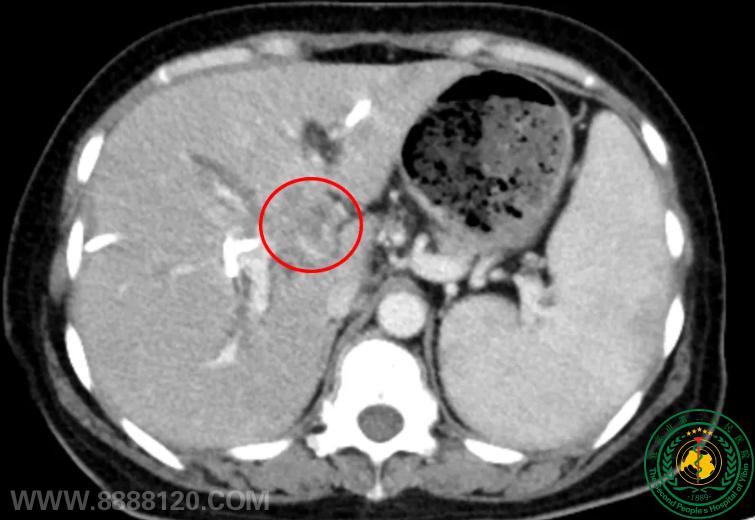

突破生命禁区!我院介入科成功完成川南首例、四川地市级医院首例经皮肝肿瘤纳米刀消融术,为肝门部恶性肿瘤患者带来新希望

突破生命禁区!我院介入科成功完成川南首例、四川地市级医院首例经皮肝肿瘤纳米刀消融术,为肝门部恶性肿瘤患者带来新希望62544